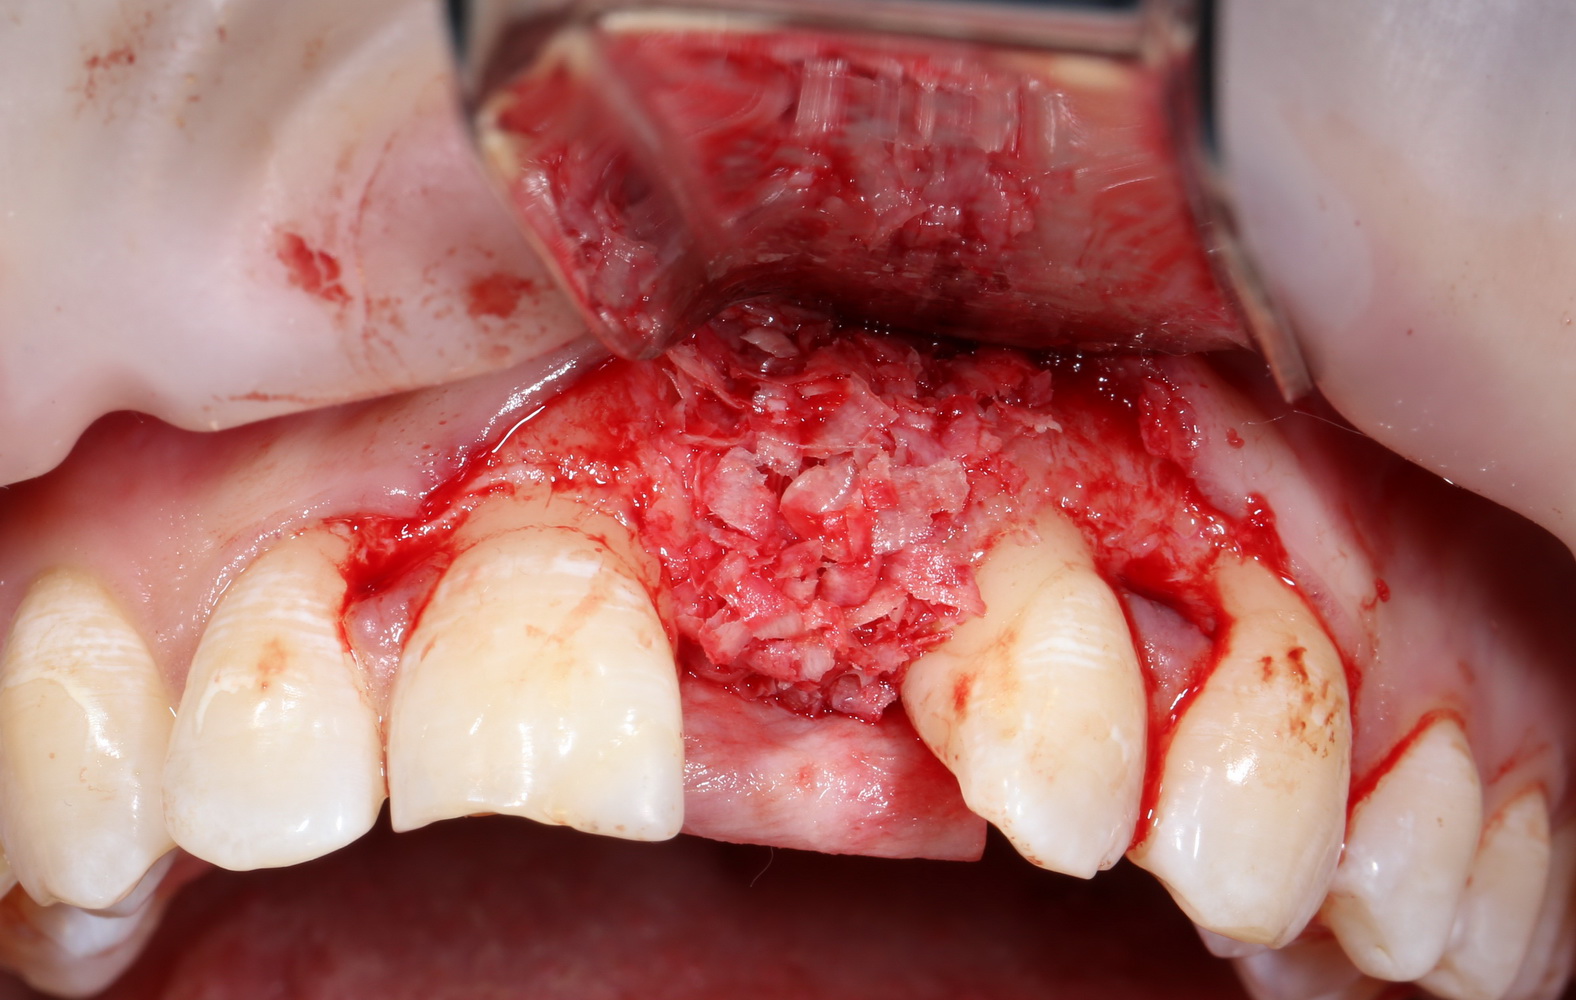

Следовательно, можно установить имплантат и «нарастить» вокруг него необходимые объемы костной ткани. Что мы и делаем:

4  8  9